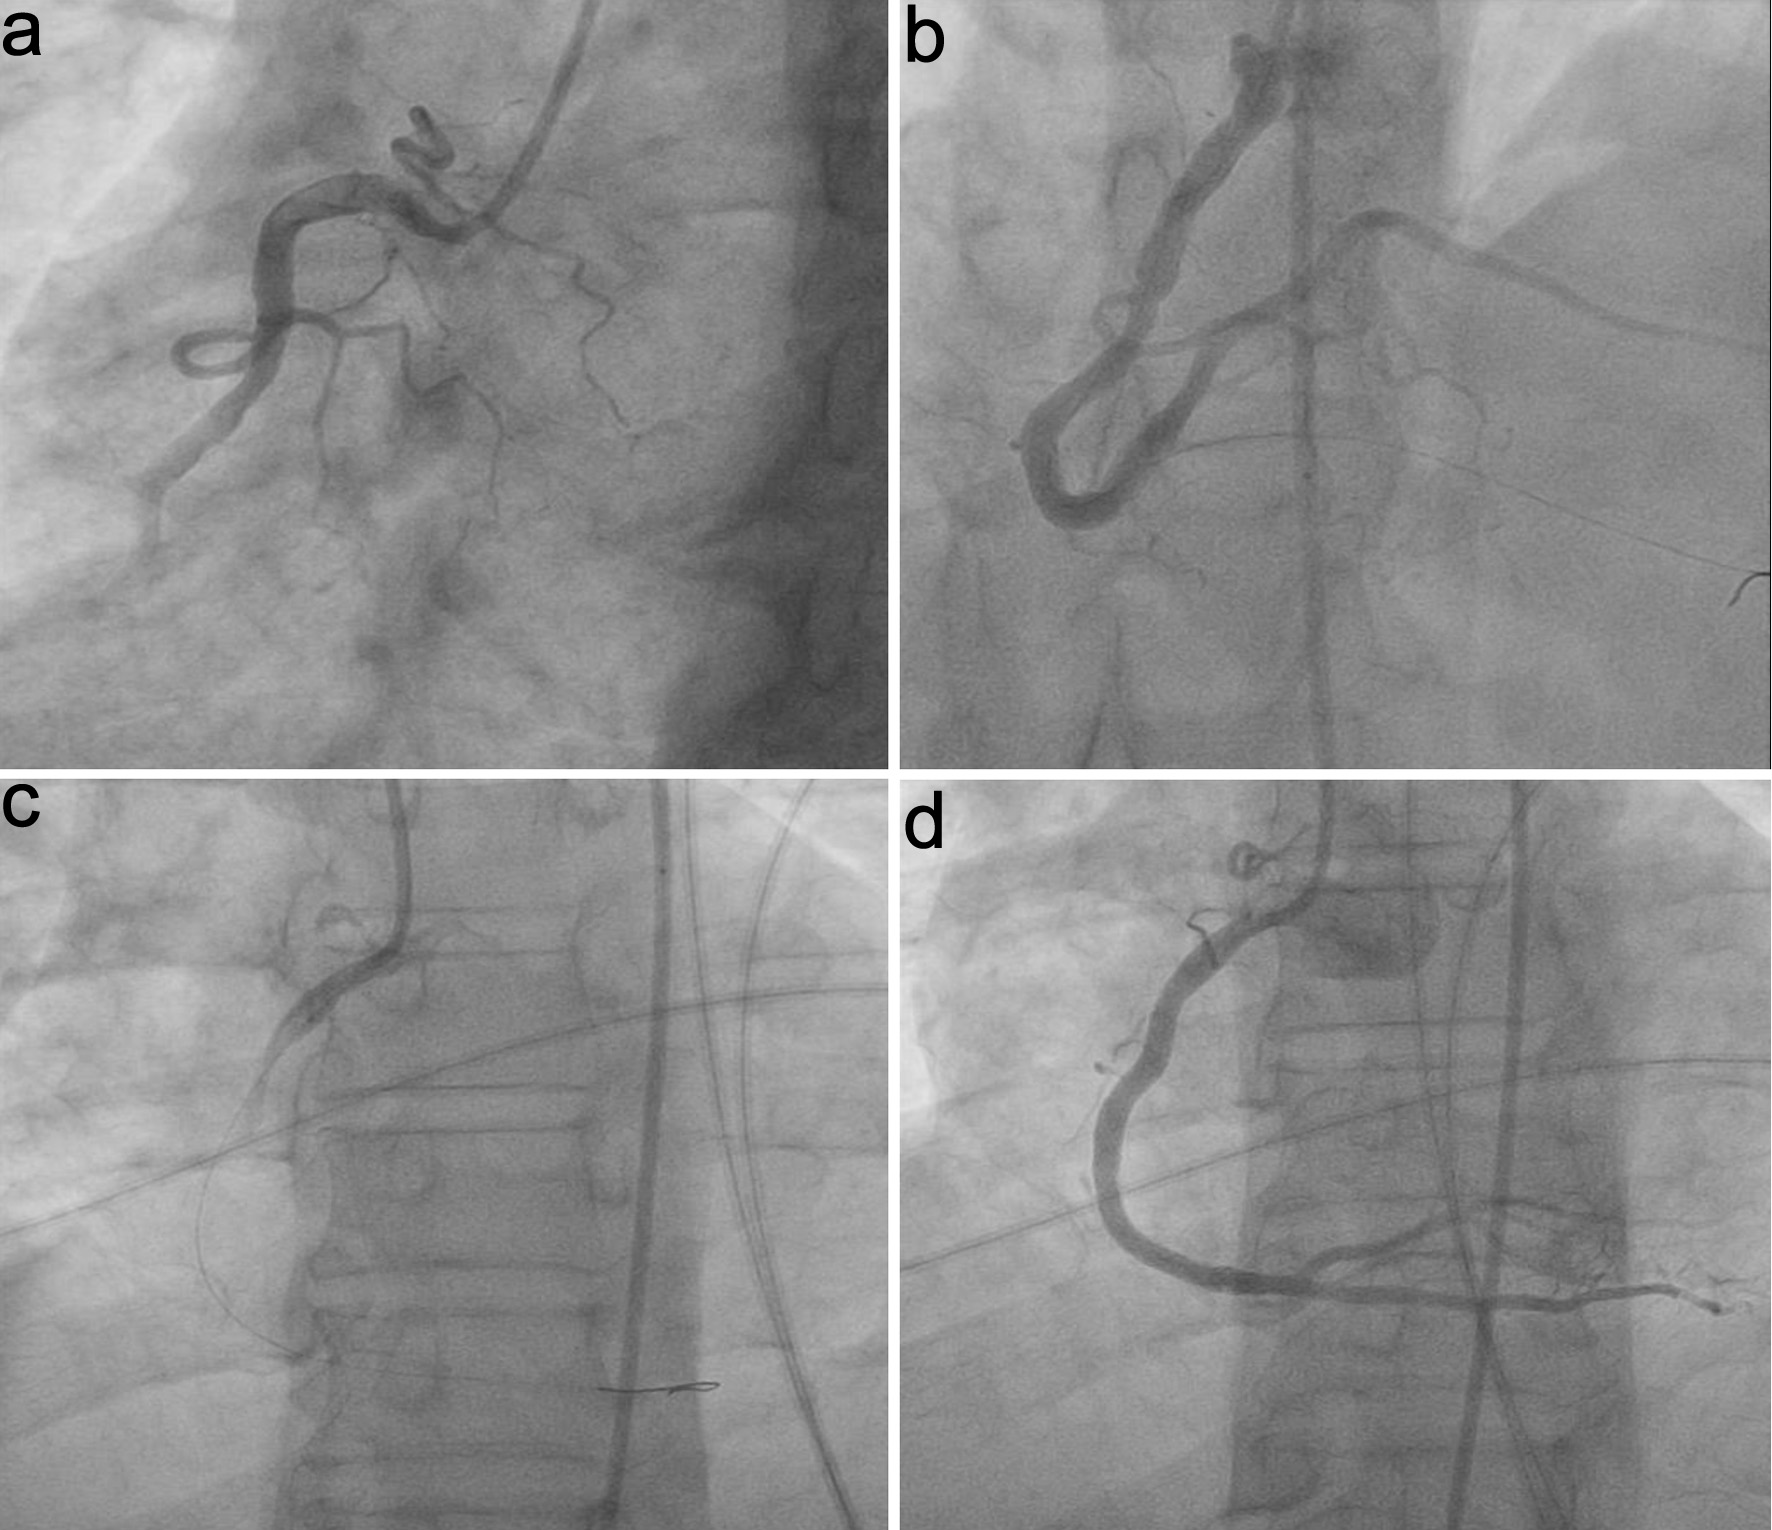

Pre-PCI TIMI flow was grade 0 in all cases. Post-tirofiban, TIMI flow grade, reflow, and ST-T normalization were notably higher in group S than group C (P = 0.041, 0.007, and 0.034). Treatment for no-reflow post-PCI (IC nitrate and diltiazem) was notably lower in group S (P = 0.007). Post-PCI balloon dilatation showed no substantial difference between groups. Minor bleeding was notably higher in group S (P = 0.026), while major bleeding did not occur in either group. Cardiac death was not notably different between groups. Total in-hospital target vessel failure (TVF) was notably lower in group S compared to group C (P = 0.012) (Table 3, Fig. 2). Representative angiographic images of the right coronary artery (RCA) before and after PCI, with and without IC tirofiban, are shown in Figure 3. Post-tirofiban administration, TIMI 3 flow was achieved, illustrating improved coronary perfusion compared to the placebo group.

Figure 3. Representative angiographic images of the right coronary artery (RCA) in STEMI patients. (a) Pre-PCI, placebo group. (b) Post-PCI, placebo group. (c) Pre-PCI, IC tirofiban group. (d) Post-PCI, IC tirofiban group, demonstrating improved TIMI 3 flow with tirofiban administration. IC: intracoronary; PCI: percutaneous coronary intervention; TIMI: thrombolysis in myocardial infarction.